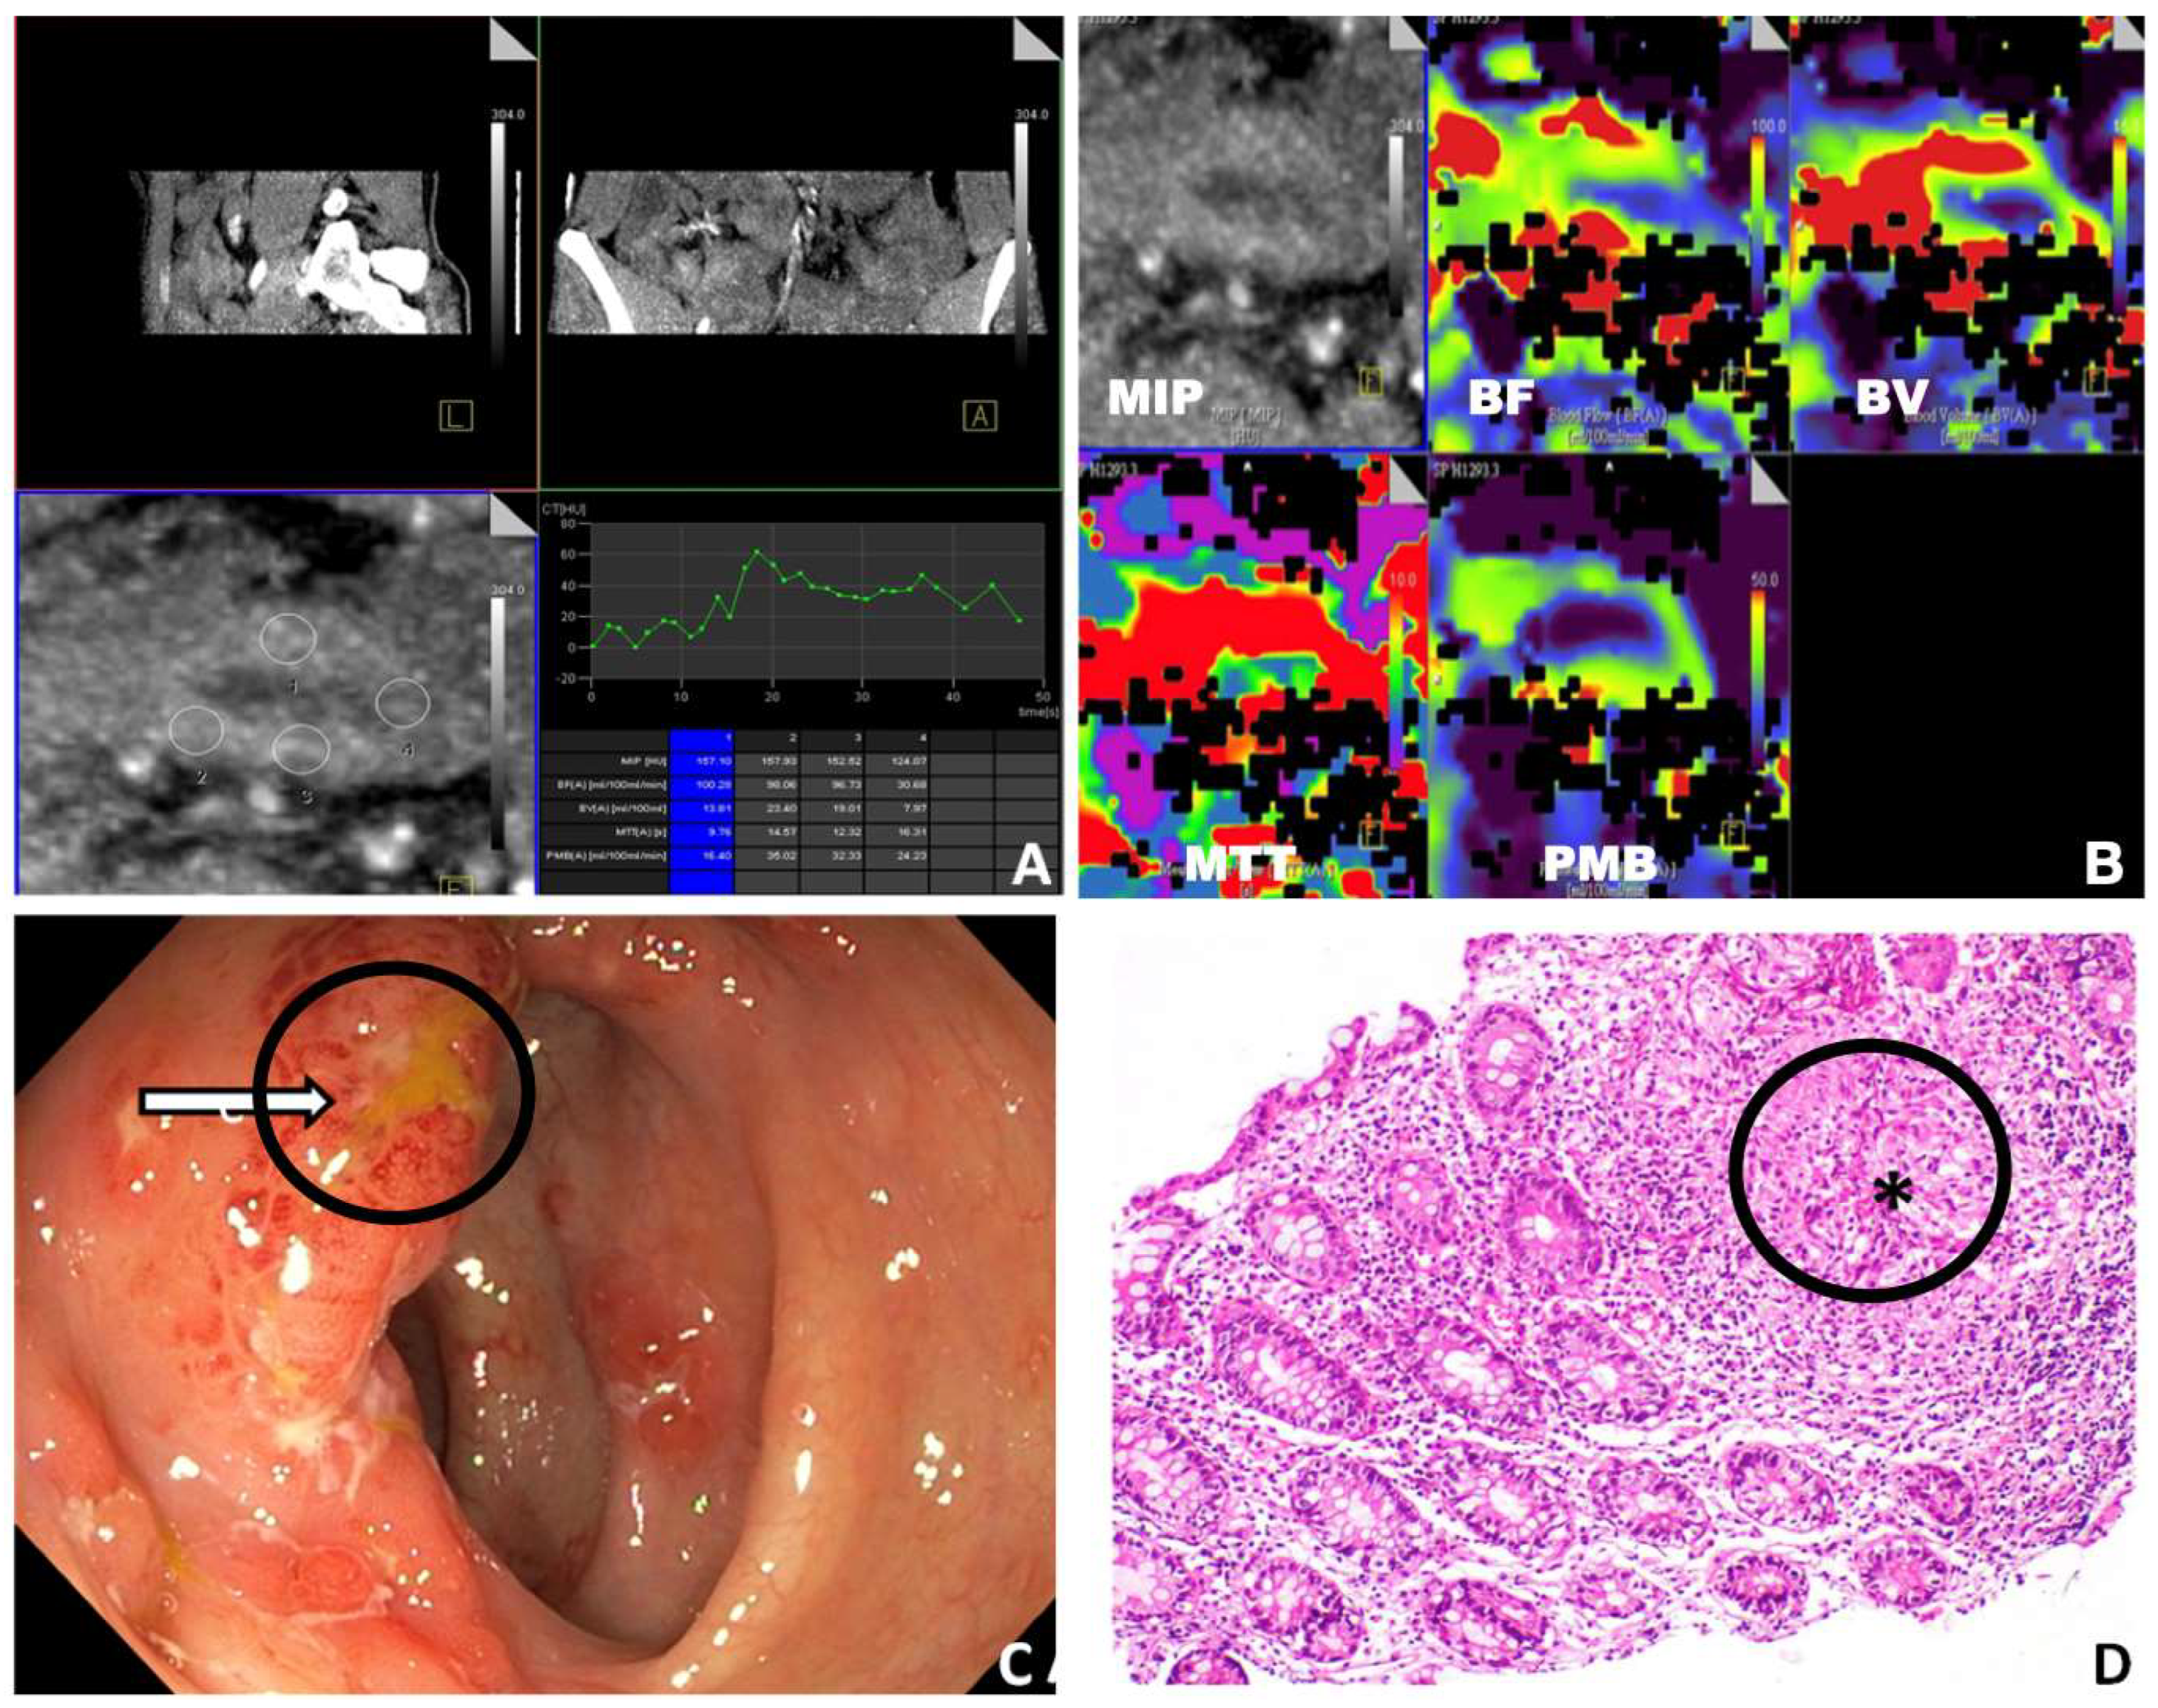

3. Results

3.2. PCT Parameters